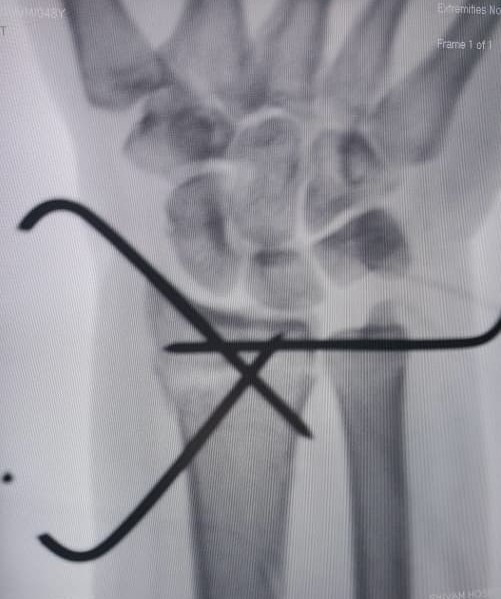

Image Gallery

Pictures That Speak

Irecently underwent surgery for a distal radius injury (CRIF with plate fixation) at Shivam Advanced Ortho Care Hospit...

I was admitted for wrist bone fracture and underwent plating surgery under Dr. Amardeep Sir. He explained the procedure,...